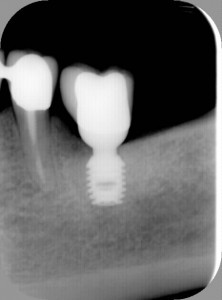

Quest’impianto, da non confondere con il mini impianto (provvisorio) è una vera rivoluzione nella chirurgia mininvasiva. Lo Short Implant consente sempre l’edentulismo parziale.

E’ terapia d’elezione,quando c’è poco osso,perchè è un impianto “corto”.

E, da circa due anni, ha generato l’ultra Short Implant, applicabile anche con

esigue dimensioni ossee.